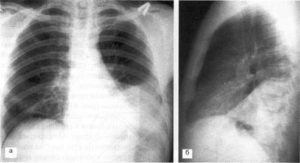

Рентгенограмма, светлая область – местонахождение экссудата.

По рентгенограмме можно определить наличие выпота и его примерный уровень, то есть получить примерное представление о количестве экссудата.

Если воспалительной жидкости в плевральной полости мало, то есть ее количество не превышает 150-200 мл, для уточнения ее наличия применяется метод так называемой латерографии.

Последний заключается в проведении рентгенологического исследования в положении пациента на больном боку. Если воспалительный экссудат имеет место быть, то на рентгенограмме станет определяться узкая лентовидная тень.

В нижней части изображения определяется затемнение (светлый участок) – это и есть полоска экссудата.